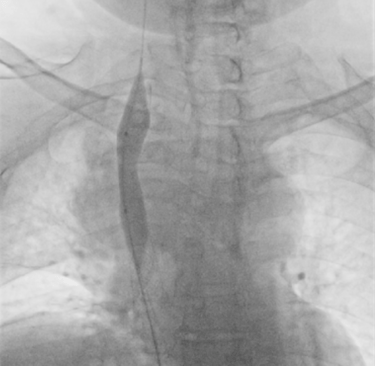

Terapia endovascular de zonas de estenosis

Procedimientos mediante intervencionismo percutaneo para tratar zonas de obstrucción y estenosis responsables de la disfunción del catéter de hemodialisis.

“Nací con hipoplasia renal y, tras un trasplante que falló, tuve que volver a la hemodiálisis. Con los años, mis venas se fueron cerrando y ya no había por dónde dializarme. El doctor me explicó que necesitaban abrir las venas que llegan a mi corazón con una angioplastia de la vena cava. Sonaba complejo, pero confié. Gracias a ese procedimiento y al equipo que lo realizó, hoy sigo en tratamiento y con una nueva oportunidad de vida.”